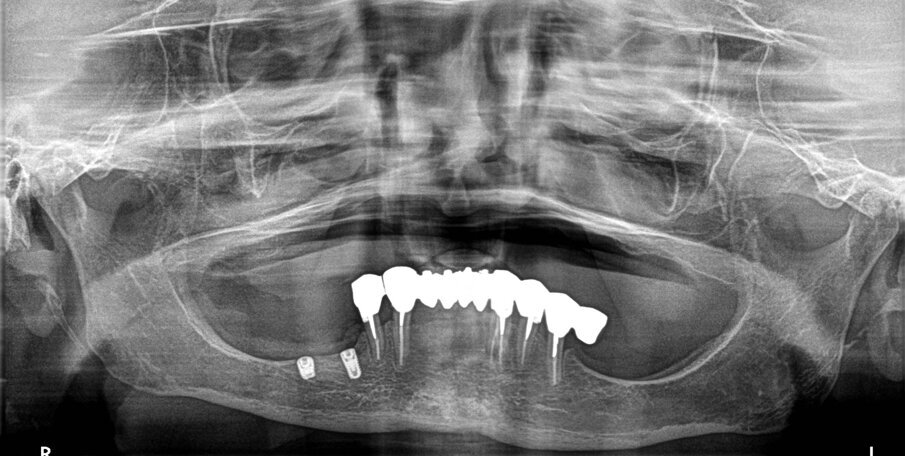

La terapia anticoagulante non è stata interrotta prima della chirurgia ed è stata somministrata la profilassi antibiotica come da protocollo. È stata eseguita un’incisione crestale senza tagli di scarico che è stata estese distalmente fino al trigono retromolare per esporre la branca mandibolare ed avere un sito per raccogliere osso autologo con una fresa carotatrice. Sono state eseguite le osteotomie a basso numero di giri come da protocollo BTI per ottenere un’ulteriore quantità di osso autologo raccolto dalle frese e inseriti due impianti BTI Core 3,75 x 4,5 e 3,5 x 6,5 rispettivamente in posizione 46 e 45.

L’osso autologo è stato mescolato con gel piastrino ottenuto da centrifugazione del sangue del paziente mediante metodica Endoret BTI. La membrana ottenuta è stata applicata a protezione della corticale vestibolare. Ulteriori membrane di gel piastrino sono state applicate sopra l’osso autologo. La stabilita primaria di entrambi gli impianti era superiore ai 50 Newton per cui sono stati avvitati i pilastri Multi-Im e i pilastri di guarigione per un tecnica con una sola chirurgia. Sono state applicate suture sintetiche non riassorbibili a punti staccati (Figg. 3–10). Successivamente è stata eseguita una Rx di controllo. Le suture sono state rimosse a due settimane e la paziente riferì di avere avuto disagi minimi, senza ematomi o edemi estesi e scarsa dolenzia che non richiese l’assunzione di antinfiammatori.